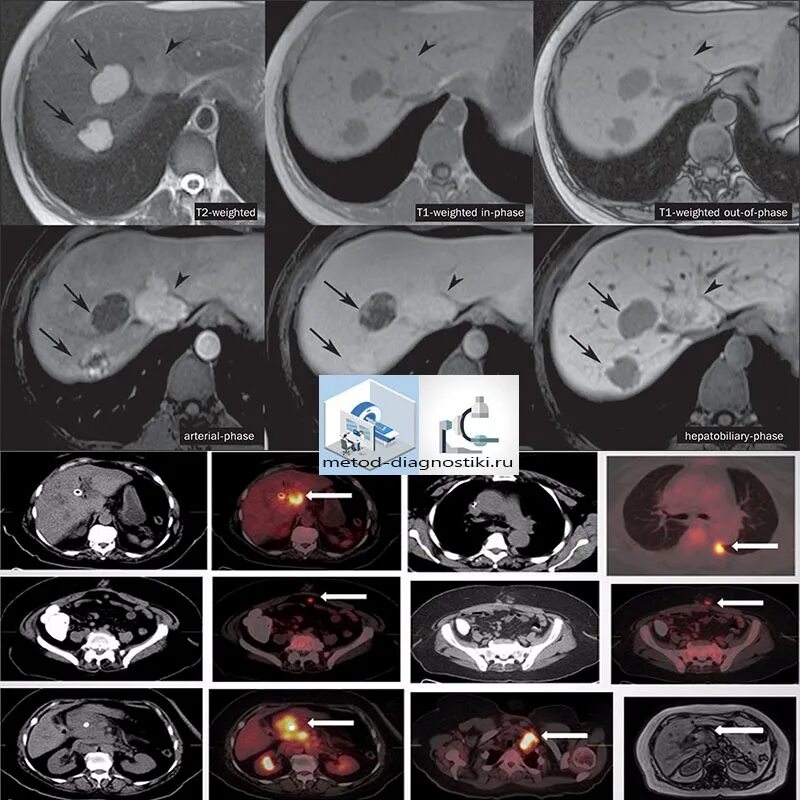

Камни в желчном мрт